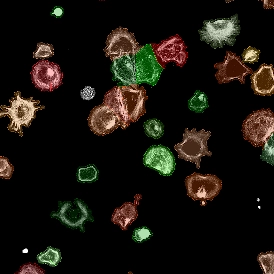

What is Imaging Mass Cytometry?

Imaging Mass Cytometry (IMC) expands mass cytometry with laser ablation and metal-tagged antibodies, enabling visualization of 40+ markers in tissue. IMC reveals cellular phenotypes in their native microenvironment, supporting research in oncology, immunology, and precision medicine.

How Does Imaging Mass Cytometry Work?

Imaging Mass Cytometry (IMC) enables visualization of 40+ markers in tissue using metal-tagged antibodies and mass spectrometry. Combined with StrataQuest analysis, IMC supports single-cell detection, co-expression studies, and spatial mapping for advanced biomedical insights.